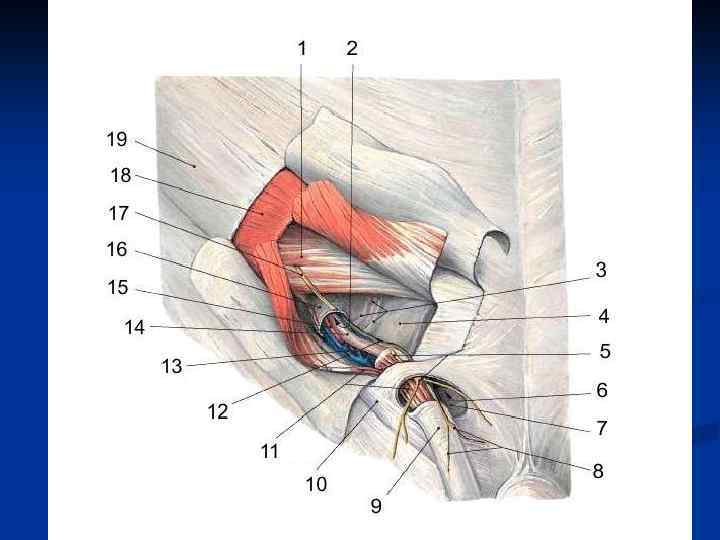

Семенной канатик, funiculus spermaticus – круглый тяж (15 -20 см) от глубокого пахового кольца до верхнего конца яичка, образующийся в процессе опускания яичка. Состав: 1. Семявыносящий проток 2. Яичковая артерия 3. Артерия семявыносящего протока 4. Лозовидное венозное сплетение 5. Лимфатические сосуды яичка и придатка 6. Нервы 7. Влагалищный отросток Оболочки, tunicae funiculi spermatici (изнутри наружу): 1. Внутренняя семенная фасция 2. Мышца поднимающая яичко 3. Фасция мышцы поднимающей яичко 4. Наружная семенная фасция

Семенной канатик, funiculus spermaticus – круглый тяж (15 -20 см) от глубокого пахового кольца до верхнего конца яичка, образующийся в процессе опускания яичка. Состав: 1. Семявыносящий проток 2. Яичковая артерия 3. Артерия семявыносящего протока 4. Лозовидное венозное сплетение 5. Лимфатические сосуды яичка и придатка 6. Нервы 7. Влагалищный отросток Оболочки, tunicae funiculi spermatici (изнутри наружу): 1. Внутренняя семенная фасция 2. Мышца поднимающая яичко 3. Фасция мышцы поднимающей яичко 4. Наружная семенная фасция